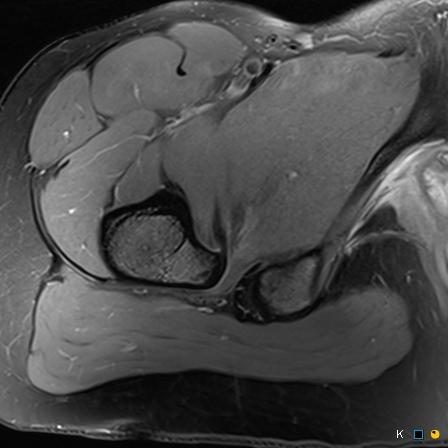

Figure 4 for case reverse slipped upper femoral epiphysis

Figure 4